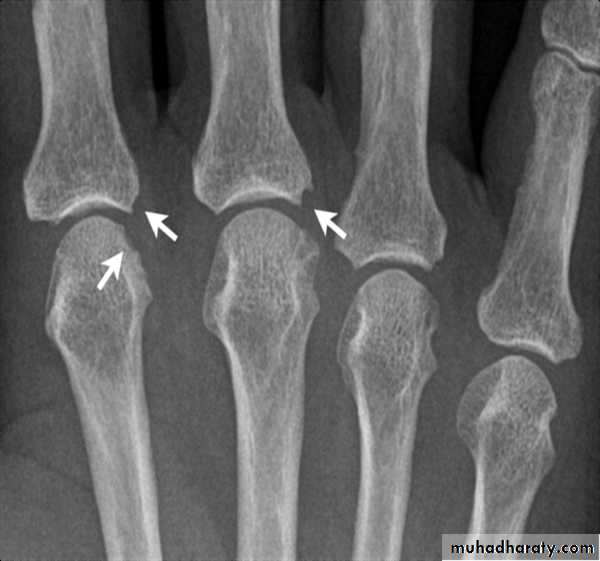

(A) The initial radiograph shows a hint of early trabecular loss around the proximal interphalangeal joint of a finger with preservation of the joint space and early marginal cortical loss at the

base of the middle phalanx.

(B) The subsequent radiograph shows established erosive change in the area of ill-defined demineralisation in association with joint space narrowing .